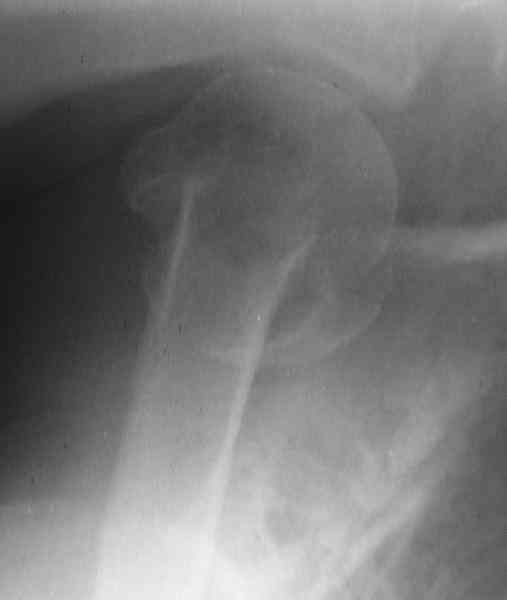

This fx need to be manipulated, reduced and fixed. We developed a minimally invasive ex fix with Ilizarov parts to fix it, we call it “Spider”, which can hold 4 fragments.

Attaching a case.